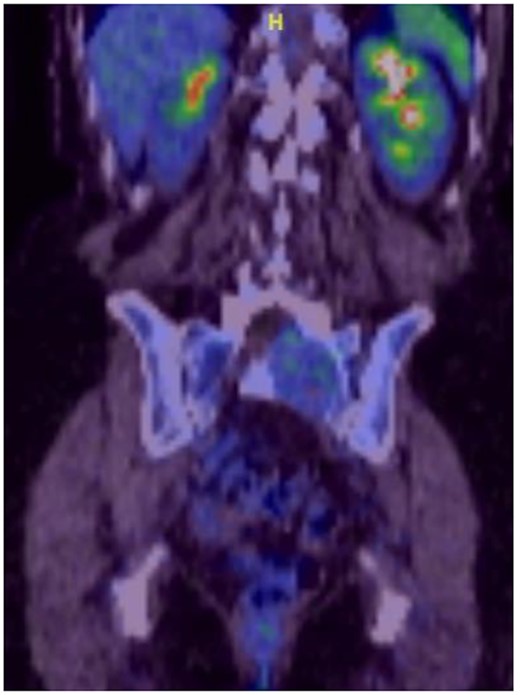

Reviews in July 2019 (with an MRI scan in December 2019) and December 2020 confirmed no neurological deterioration but some increased back and leg pain when standing for some time. A repeat MRI scan confirmed an increase in the size of the lesion (Figs 1 and 2). A biopsy was arranged with a plan for a follow-up surgery. Results of the CT-guided biopsy indicated a diagnosis of metastatic malignant melanoma. Discussions with the patient did not localise any skin lesion responsible for the metastatic deposit, an F18-fluorodeoxyglucose positron emission tomography (18F-FDG PET/CT) scan and a conventional computed axial tomography (CT) scan was organised (April 2021), which revealed sacral destruction and no other deposits in the chest, abdomen and pelvis (Figs 3 and 4). Our patient had a reported SUV of 3.6, indicating a malignant lesion that was then confirmed operatively.

MS comprises <1% of primary peripheral sheath tumours. The most common sites are cervical and upper thoracic spinal nerves with 30–40 years being the most common age group of occurrences [1, 3, 9]. The MRI characteristics of high signal on T1WI and low signal on T2WI with homogenous enhancement with contrast are well known. Our patient was in an older age group during presentation and had no skin deposits. Whereas a diagnosis was made on biopsy, it is also possible to use the FDG uptake on PET/CT imaging to determine the benign or malignant nature of the tumour [1]. The standardised uptake value (SUV) is a simple way of determining activity in PET imaging, most commonly in FDG imaging, and can predict the histologic response [10, 11]. It is used to measure response of cancers to treatment and considered a semi-quantitative value as it is vulnerable to other sources of variabilities [10, 11]. Hamada et al. set the cut-off point to 3.0 for distinguishing benign and malignant lesions [12]. Whereas there is an overlap in the SUV cut-off point amongst various authors, there is also a wide variation between them [13, 14]. Ahmed et al. reported 0.33–3.7, whereas Aoki et al. reported 1.75 ± 0.84 [14, 15]. However, Aoki et al., in another paper, reported a wider range of 0.7–2.84 [13]. Our patient had a reported SUV of 3.6, indicating a malignant lesion that was then confirmed operatively.